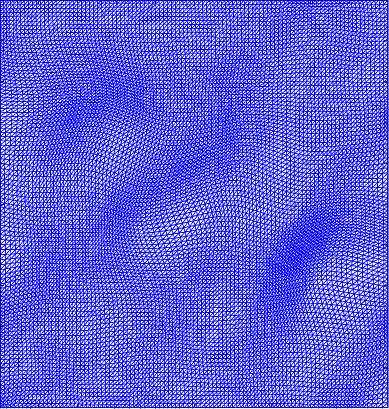

Figure 4 shows the visualisation of Figure 3 mappings in the form of grids. Let and be the Beltrami coefficients of the registration maps from the reference frame to the ground truth frame in Figure 3(a) and the perturbed frame in Figure 3(b) respectively. Figure 4(a) shows the mapping associated to Beltrami coefficient , and Fig 4(b) shows the mapping associated to BC . From Figure 4(c) and Fig 4(d), we can see that our method successfully restored the normal and abnormal deformation. Figure 4 serves as evidence that our decomposition is meaningful, in the sense that our method does not blindly return a Beltrami Descriptor with certain periodicity, but the decomposed descriptor does carry our desired information to recover the deformation to a large extent.